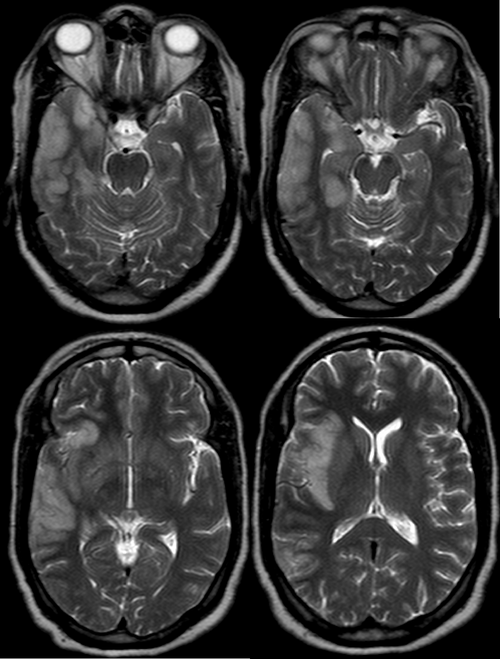

(图片来源网络,侵删)